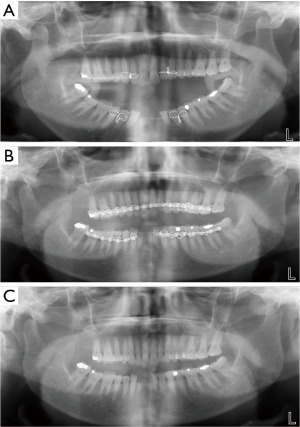

On arrival at A&E, the trauma team initiated further investigations. A trauma series confirmed bilateral anterior TMJ dislocation with no evidence of mandibular fracture or dental trauma (Figure 1A). Initial attempts at manual closed reduction using the traditional two-thumb technique under sedation with intravenous (IV) midazolam were unsuccessful due to persistent muscle rigidity and jaw clenching. Due to the patient’s increasing discomfort and the mechanical difficulty resulting from severe dystonia, a reduction under general anaesthesia was arranged.

Under anaesthesia, muscular relaxation was achieved, allowing successful reduction of both TMJs with a satisfying bilateral click (Figure 1B) by the oral and maxillofacial surgical team. Stabilising elastics and braces were applied to minimise the risk of recurrence. Post-reduction, the patient was closely monitored and a soft diet was advised.

At the outpatient oral and maxillofacial review four weeks later, the braces and elastics were removed (Figure 1C). He had made a full anatomical and functional recovery, with no further dislocation or restriction in jaw movement. His mental state had also stabilised, supported by closer GP and CMHT follow-up. His treatment plan was modified to include more regular community reviews, adherence monitoring, and education on early signs of extrapyramidal side effects to prevent recurrence (Table 1).